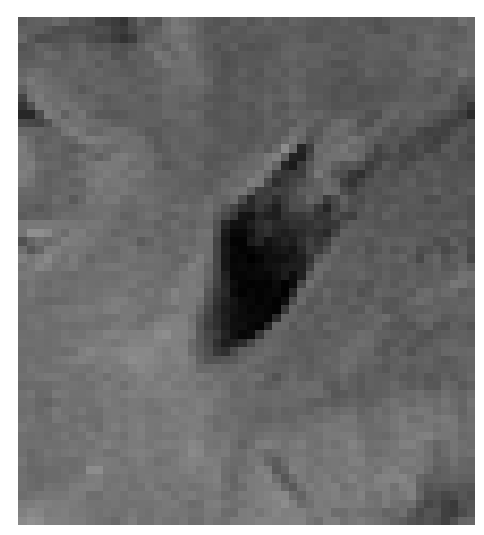

Figure 3: Reconstructions results. Rows 1 and 3: Examples of comparing the ground truth (GT) fully sampled image to the reconstructed images obtained by the three models (1-3), NPB-REC, baseline, E2E-VarNet trained with Dropout, and the NPB-REC std. map at accelerations R=4𝑅4R=4, R=8𝑅8R=8, respectively. Rows 2 and 4: The corresponding annotated ROIS of Nonspecific white matter lesions.

Fig. 3 presents examples of reconstruction results obtained by (1) our NPB-REC approach, (2) the baseline, and (3) Monte Carlo Dropout, for equispaced masks with two different acceleration rates R=4𝑅4R=4 and R=8𝑅8R=8. The reconstructed images predicted by the three models are smoother than the reference image. This is due to the fact that all the models were trained with SSIM loss, which tends to produce overly smooth reconstructions while preserving the diagnostic content and the anatomical features Sriram et al. (2020a). These images can be enhanced by dithering the image by adding a small amount of random Gaussian noise to produce a more textured reconstruction, as proposed in Sriram et al. (2020b).

Table 1 presents the mean PSNR and SSIM metrics, calculated over the whole inference set, for the three models. Our NPB-REC approach achieved significant improvements over the other methods in terms of PSNR and SSIM (Wilcoxon signed-rank test, pmuch-less-than\ll1e-4, except for SSIM values in line W, R=4𝑅4R=4 where they are roughly the same for NPB-REC and Baseline). The improvement in the reconstruction performance can be noted both quantitatively from the metrics, especially for masks with acceleration rate R=8𝑅8R=8, and qualitatively via the images of annotations, where our results show less smoothness than those obtained by Dropout.